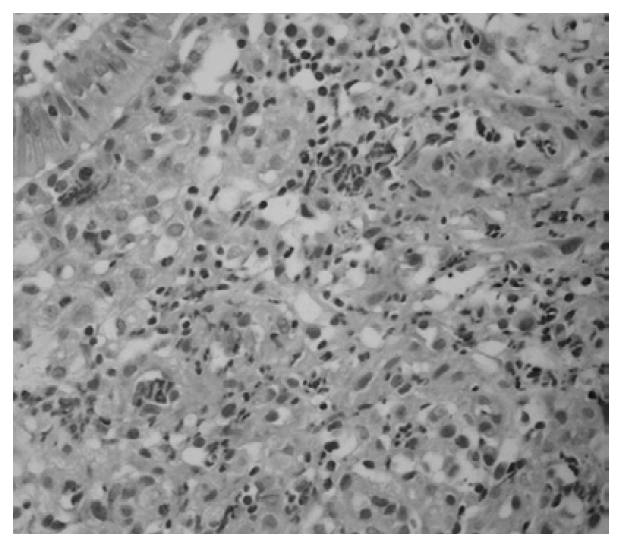

A 20-year-old woman was admitted to hospital because of arthralgia on both ankles and palpable purpura on both legs for 5 days. Physical examination showed multiple purpura on legs and buttock and swelling and tenderness on both elbows and ankles (Figure 1). Laboratory data showed normal blood counts, blood chemistry and urine analysis. C-reactive protein was 3.7 mg/dL and ESR was 21 mm/hr. Tests for antinuclear antibody, rheumatoid factor and antineutrophil cytoplasmic antibody (ANCA) were negative. Serum concentrations of immunoglobulin (Ig)G, IgA, IgM, C3 and C4 were normal. A biopsy specimen of skin lesions showed leukocytoclastic vasculitis and immunofluorescent study revealed IgA depositions on vessels (Figure 2).